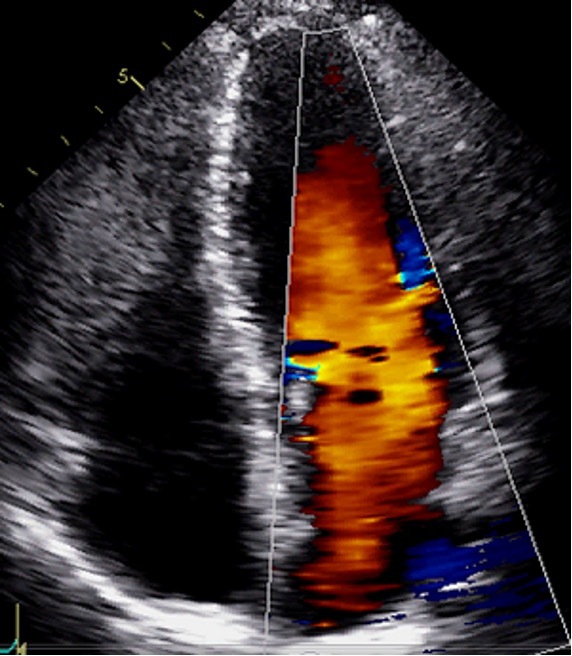

For colour doppler what will stenosis show?

Aliasing

During colour doppler what will regurgitation show?

A bit of aliasing right at the valve, unless the leak is really big

The LVOT and AV colour doppler here is what?

Aliased in the normal heart